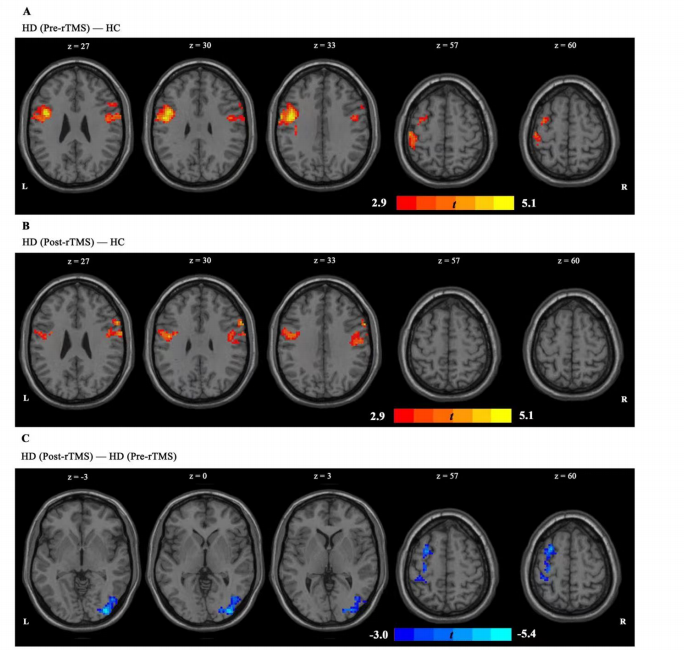

上圖為經(jīng)顱磁刺激后左側(cè) IPL 與全腦網(wǎng)絡(luò)之間的功能連接,采用雙樣本t檢驗(yàn)。A圖顯示,與 HC組相比,HD(治療前)組左側(cè)IPL-左中央前回偶聯(lián)和左側(cè)IPL-右額下回耦聯(lián)增加。B圖顯示,經(jīng)rTMS治療后,HD組左IPL-左中央前回耦聯(lián)和左IPL-右額下回耦聯(lián)異常增加明顯減少,在完成 7 個(gè)療程的 rTMS 治療后,呈接近HC組的趨勢(shì)。C圖顯示 rTMS 對(duì)左側(cè)IPL-左側(cè)額中回偶聯(lián)和左側(cè)IPL-右側(cè)枕下回耦聯(lián)有顯著影響。在這兩個(gè)區(qū)域,經(jīng)過 7 次經(jīng)顱磁刺激療程后,功能連通性顯著下降。

上圖為經(jīng)顱磁刺激后右側(cè) IPL 與全腦網(wǎng)絡(luò)之間的功能連接。

A圖顯示,HD組(治療前)的右側(cè) IPL-左側(cè)中央前回偶聯(lián)和右側(cè) IPL-右側(cè)中央前回偶聯(lián)均有所增加。B圖顯示,在 7 個(gè)療程的經(jīng)顱磁刺激后,這些異常增加的連接減少了